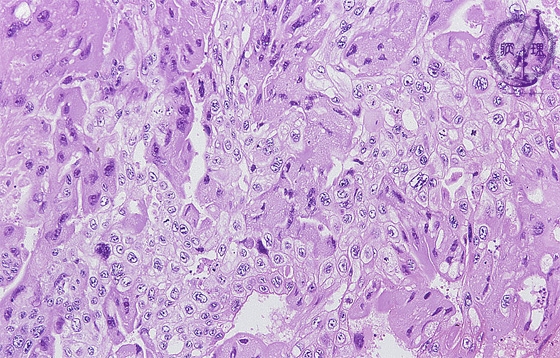

Histology (HE stain, low power):Multinucleated eosinophilic tumor cells mimicking syncytiotrophoblasts, (yellow dotted line) and tumor cells with clear cytoplasm mimicking cytotrophoblasts (blue dotted line) proliferate in sheet-like pattern. The former type of tumor cells produces and secretes human chorionic gonadotropin (h-CG) as identified by IHC (see below).